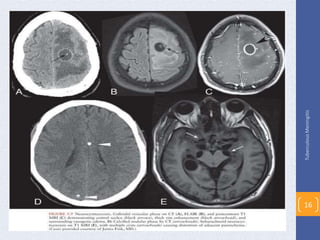

Radiographic studies

CT or MRI - brain

• Normal during early stages of the disease

• As disease progresses

Basilar enhancement

Communicating hydrocephalus

Signs of cerebral edema

• One or several clinically silent tuberculomas

Most often in the cerebral cortex or thalamic regions

Diagnosis

• CT or MRI – brain

Discrete lesions with surrounding edema

Contrast medium enhancement shows ring-like lesion